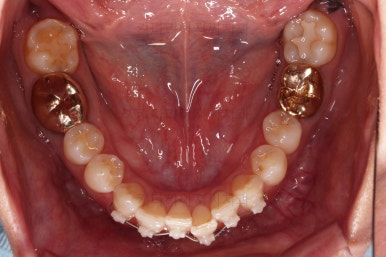

아랫니가 많이 보이지 않는 타입이라서 잘 몰랐는데 입안을 관찰해 보니 아래 앞니가 삐뚤어 있네요.

아래 앞니는 부분교정에 필수인 치간삭제를 병행하면서 많이 가지런해지고 있습니다.

아랫니 부분교정이 끝났고요.

치료 종료시의 모습인데요.

임플란트가 잘 들어갔고 아래 앞니도 원하는 모습으로 잘 배열이 되었습니다.

부산치아교정비용 전후 비교해 볼게요.

치료기간은 임플란트의 안정성 때문에 길어지긴 했으나 사실상 내원횟수는 그리 많지 않으셨고, 교정장치가 눈에 보이는 기간은 7개월정도 밖에 안되었기 때문에 크게 문제되지는 않았던 것 같습니다.

여러 가지가 다 잘 마무리 되었습니다.

이상 아래 앞니 부분교정 및 임플란트를 위한 어금니 부분교정 이후 임플란트까지 완성한 치료사례였고 부산치아교정비용과 가격도 대략 알아보는 시간이었습니다.